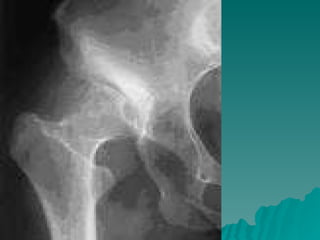

Developmental dysplasia of the hip is a condition where the hip joint is unstable or partially dislocated. It affects 1-50 out of every 1000 live births, with 60% being detected by 1 week of age and 90% by 8 weeks. The document discusses the anatomy, aetiology, pathology, clinical features, imaging, and different treatment approaches depending on if the patient is under 6 months, 6 months to 6 years, or above 6 years of age.